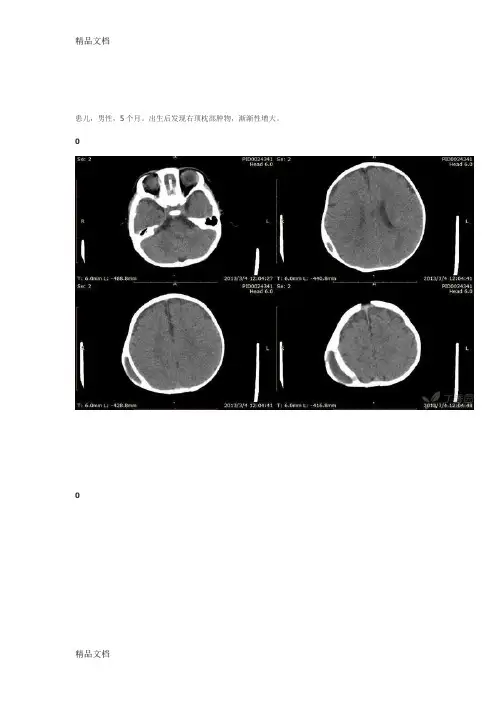

患儿,男性,5个月。

出生后发现右顶枕部肿物,渐渐性增大。

影像:右侧顶骨内见类梭型软组织密度影,密度均匀,边界清晰,病灶未跨越骨缝。

考虑:1、颅骨骨膜下出血:积血位于外层骨膜下,因此止于骨缝处,其发生率随产钳助产的应用明显增高,通常生后迅速增大,形成一坚硬、紧张的肿块,最后形成钙化。

首先考虑。

2、膜状腱膜下血肿,表现为较硬,有波动的肿块,生后逐渐长大,2-3w吸收。

3、皮样囊肿相关疾病:∙诊断右侧顶部骨膜血肿机化(非帽状腱膜)依据:1、男性,5个月。

2、右顶部颅板梭形增厚,以颅骨内板增厚为主,外板稍膨胀,内外板之间见梭形软组织密度影。

诊断分析:病灶呈梭形,张力较高,符合骨膜撕裂并出血的特点(帽状腱膜组织非常疏松,一旦损伤就是一圈),本例的原因可能为小儿足月难产或胎儿较大或胎位不正等,而致出生时产道挤压伤或胎盘吸引器损伤,最后导致骨膜撕裂而出血,患儿出生后血肿逐渐增大并机化、钙化。